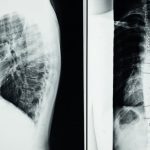

Le pincement discal lombaire est une condition courante qui survient lorsque les disques intervertébraux de la colonne vertébrale subissent une pression excessive, entraînant des douleurs significatives et une limitation des mouvements. Les disques agissent comme des amortisseurs entre les vertèbres, mais lorsque l’espace entre ces disques est réduit, cela peut provoquer une compression des nerfs environnants, ce qui conduit à des symptômes tels que des douleurs lombaires, des engourdissements ou des faiblesses dans les membres.

La décompression neurovertébrale se base sur un principe scientifique : en réduisant la pression sur les disques intervertébraux, on peut améliorer la circulation sanguine et encourager la réhydratation des disques. De cette manière, le processus de guérison est non seulement accéléré, mais la flexibilité des disques est également améliorée. Cela aide à soulager la douleur et optimise le fonctionnement de toute la colonne vertébrale.

La décompression neurovertébrale fonctionne grâce à un processus délicat, où la colonne vertébrale est étirée de manière contrôlée, réduisant la tension sur les nerfs et les tissus environnants. Cette méthode contribue à diminuer la douleur, à optimiser la circulation sanguine vers les structures du dos et à soutenir le processus de réhydratation des disques intervertébraux.